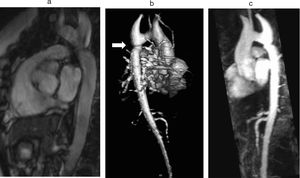

B. Aortic abnormalitiesB.1. Coarctation of the aortaCoarctation of the aorta (CoA) affects around 12% of women with TS11 and is usually diagnosed in infancy, often with congestive heart failure in critical cases17 (Figure 3).

Coarctation of the aorta (white arrow) in a 24-year-old TS woman in different projections: (a) sagittal-oblique cine magnetic resonance image, (b) volume-rendered magnetic resonance aortography (posterior-oblique view), (c) magnetic resonance aortography maximum intensity projection (sagittal-oblique view).

Indeed, in contrast to BAV, which is detected by screening, CoA is usually diagnosed based on clinical grounds – HTN and brachial-femoral delay are common features. However, since many cases are detected later in life, any woman with suspected CoA should have a CMR or computed tomography (CT) angiography with three-dimensional reconstruction of the thoracic aorta.1,11